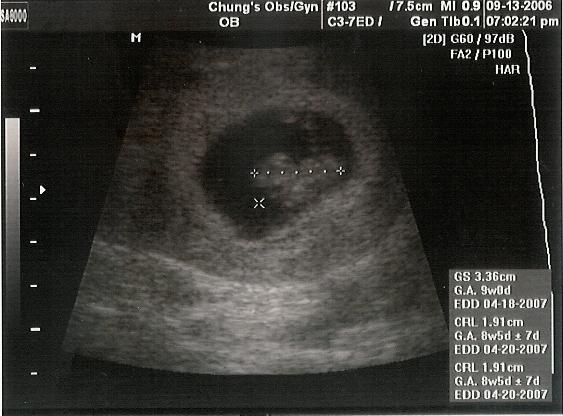

這個是8週半~~